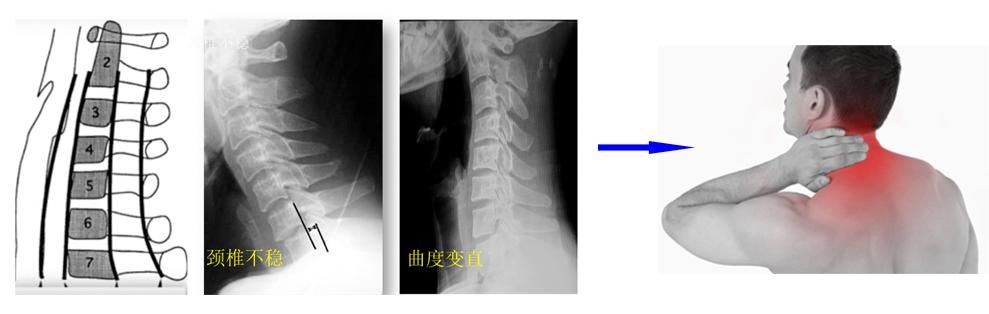

(1)颈型颈椎病: 主要是由于椎间盘退变后,椎体关节之间不稳定所致,椎体关节的不稳定会导致颈部肌肉韧带代偿工作,长期会引发疲劳,因此颈型颈椎病的主要临床症状就是颈肩痛,且伴有颈背部压痛。这类颈椎病以青壮年(30-40岁)多发,晨起(睡觉姿势不当)、或长期劳累、低头伏案工作后出现,泡澡后或休息后有所缓解。拍摄X线片常显示:颈椎曲度变直或反弓,或椎间隙变窄,颈椎退变,颈椎骨赘增生,颈椎不稳等。